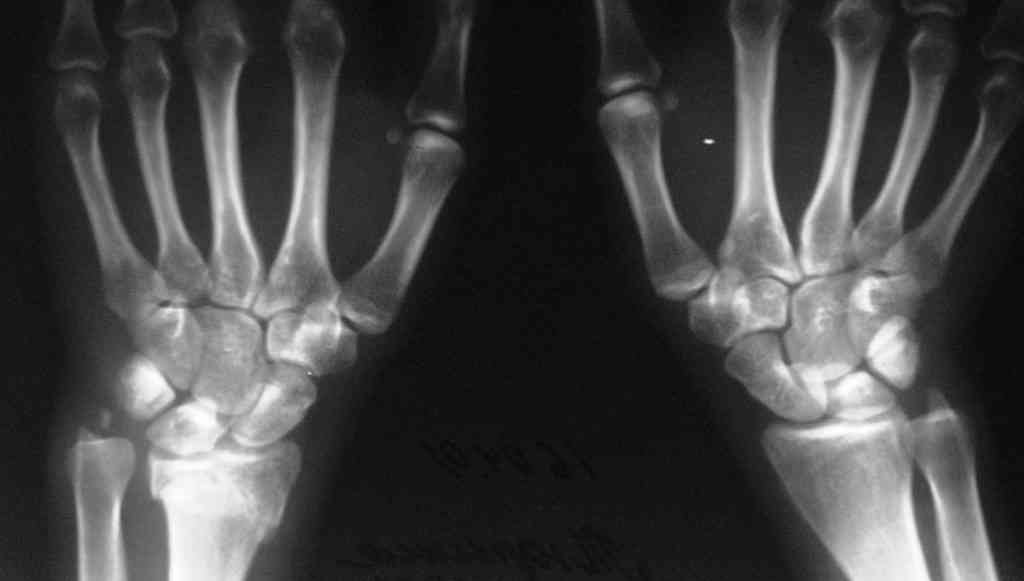

Судя по показанным Рг граммам, очевиден посттравм. артроз лучезапястного сустава, проблема дистального радиоульнарного сочленения(TFCC).

Угол наклона лучевой фасетки в норме в пределах 10-15 градусов, на представленном боковом снимке -может быть чуть больше 15градусов. Выполнив

разгибательную остеотомию луча, ты поставишь фасетку в нейтральное положение и таким образом увеличится угол разгибания , но уменьшится сгибание. По сути, амплитуда движений останется такой же.

Первым этапом я бы убрал пластину с последующей ограниченной резекцией головки локтевой кости(hemiresection and interposition arthroplasty Bowers technique). провести курс реабилитации. если уровень мобильности сустава не

будет устраивать больного, можно рассмотреть проксимальную карпальную резекцию в качестве последующего этапа.

Не думаю, что несращение локтевой кости является критичным в данных условиях, когда необходимо добиваться её консолидации - в условиях

контрактуры радио-ульнарного и лучезапястного сустава . Описана техника создания дистального радиоульнарного артродеза с преднамеренным созданием псевдоартроза локтевой кости( ограниченная резекция её на уровне

дистального метадиафиза - Сауве-Капанджи). Посмотри описание в Кэмбел 4 том, 10 -ое издание , стр. 3577.